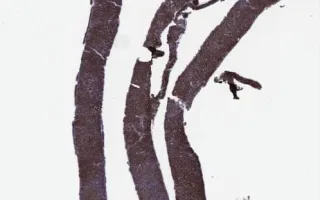

Soft Tissue, Small lymphocytic lymphoma/Chronic lymphocytic leukemia, CD20 stain

This slide shows CD20 stain. H&E stain and immunohistochemistry for CD5 and CD23 are included in the Related Content section. The case was negative for Cyclin D1, CD10, BCL6 and CD30 (not shown).

Small lymphocytic lymphoma (SLL) and Chronic lymphocytic leukemia (CLL) are essentially synonymous terms for a B cell neoplasm that shows aberrant CD5, CD23 expression. B cell markers (CD19, CD20, PAX5) are expressed, although CD20 is generally dim on flow cytometry. Importantly, CD20 can be lost in response to anti-CD20 treatment (ex. rituximab, Rituxan®). Other B-cell markers are generally preserved, with CD19 and CD79A available for flow cytometry. CD79A and PAX5 are available for immunohistochemistry.

Histologically, there is diffuse effacement of architecture with proliferation centres, which are characteristic. Scattered proliferation centres are seen in this specimen. As the name suggests, cells are small lymphocytes with clumped chromatin, with usually round nuclei. Mitotic activity/proliferation index are generally low (10% in this case).